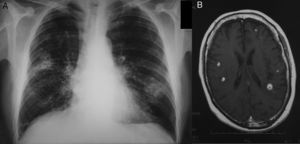

En la exploración física presentaba fiebre de 37,9°C, presión arterial de 135/78mmHg, frecuencia respiratoria de 28rpm y cardiaca de 103lpm, y en la auscultación pulmonar, crepitantes finos bilaterales. El hemograma mostraba 16.600 leucocitos y 303.000 plaquetas, y la bioquímica era normal (incluyendo pruebas de función hepática y procalcitonina), salvo una proteína C reactiva de 5,7mg/dl. La gasometría arterial basal mostraba: pO2 63mmHg, pCO2 36mmHg, pH 7,43 y saturación de oxihemoglobina 91%. En la radiografía simple de tórax posteroanterior presentaba un infiltrado alveolar cavitado en el lóbulo superior derecho y otro en el lóbulo inferior izquierdo sin cavitación (fig. 1A).

Se extrajeron 2 hemocultivos (medio aerobio y anaerobio) y se inició tratamiento empírico con piperacilina-tazobactam. La antigenuria de neumococo y Legionella fueron negativas. Tras 4días de tratamiento antibiótico sin mejoría se realizó una TC toracoabdominal en la que se confirmaban los hallazgos radiológicos previos sin otras alteraciones. En ambos hemocultivos se aisló Rhodococcus equi, cambiándose el tratamiento, según antibiograma, a imipenem, rifampicina y gentamicina. Tras 10días de ingreso el paciente comenzó con cefalea e inestabilidad, realizándose RMN cerebral (fig. 1B), en la que se observaban 8 lesiones nodulares subcentimétricas corticosubcorticales compatibles con abscesos cerebrales.